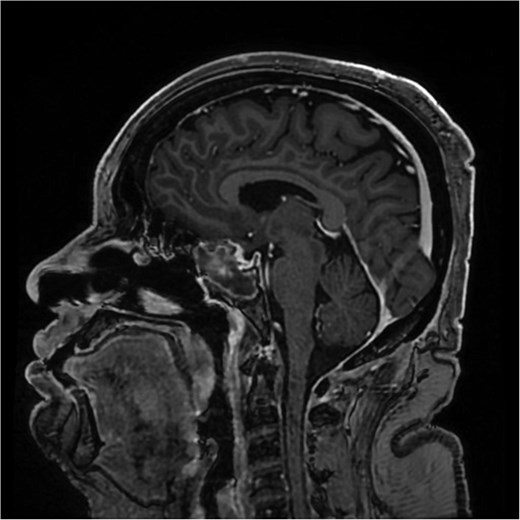

The initial evaluation included a brain magnetic resonance imaging (MRI), showing a small pituitary mass measuring 1.3 × 2.1 × 1.9 cm with suprasellar extension, neighboring the optic chiasm (Figs 1 and 2). Laboratory results revealed a high prolactin level of 110 ng/ml and normal thyroid function tests. A pituitary macroadenoma, specifically a prolactinoma, was presumed, and cabergoline was initiated.

A sagittal brain MRI reveals the same mass with superior extension to the sellar and suprasellar regions. The lesion is exerting a compression to the optic chiasm. The mass effect extends posteriorly toward the clivus, with irregular margins indicating invasive potential. Adjacent structures like the pituitary stalk appear to be displaced.